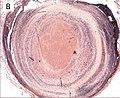

Lines of Zahn are a characteristic of thrombi[1] that appear particularly when formed in the heart or aorta. They have visible and microscopic alternating layers (laminations) of platelets mixed with fibrin, which appear lighter and darker layers of red blood cells.[2] Their presence implies thrombosis at a site of rapid blood flow that happened before death. In veins or smaller arteries, where flow is not as constant, they are less apparent.

Lines of Zahn are only seen when thrombi is formed in flowing blood as it is a distinguishing marker between ante-mortem and postmortem thrombi formation.